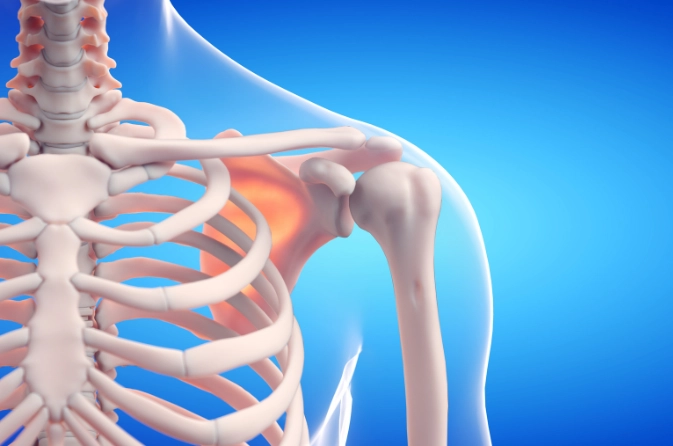

What Is Shoulder Replacement Surgery?

Shoulder Replacement is a surgical procedure where damaged parts of the shoulder joint are replaced with artificial implants. This surgery helps relieve chronic pain, restore smooth movement, and improve arm strength. It is recommended for severe arthritis, rotator cuff tears, or major joint injuries that do not respond to medication or physiotherapy.